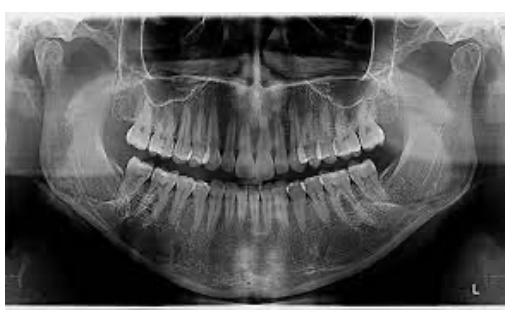

Uma mulher de 81 anos de idade, hipertensa, diabética, dislipidêmica e com disfunção temporomandibular, em uso de enalapril, hidroclorotiazida, metformina, atorvastatina e, recentemente, duloxetina, por queixa de choro fácil e pouca vontade de realizar as atividades, com o alto cuidado piorando aos poucos, foi ao serviço de emergência com quadro de importante dificuldade de abertura da boca há dois dias, associado à forte dor local, sem outros achados associados e negando ativamente outros sintomas. Ao exame físico: lúcida; pouco colaborativa com o exame físico; abertura da boca limitada, com crepitação de região de ATM; FC de 67 bpm; FR de 17 ipm, tax. 36,1⁰; e MV presente, bilateralmente, sem ruídos adventícios.